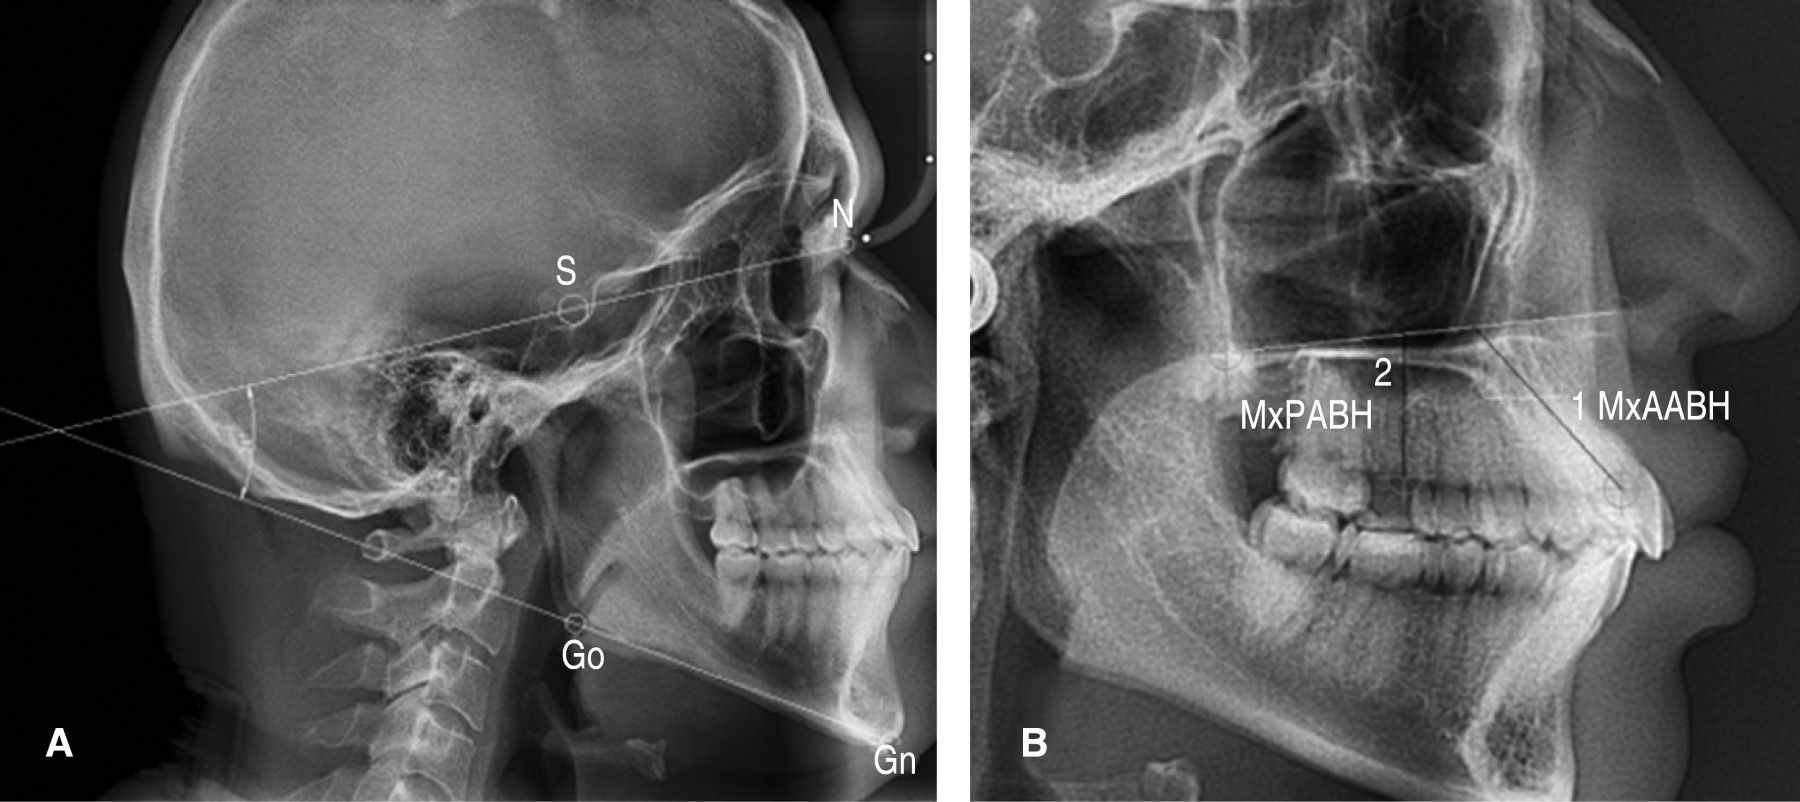

Según Cecil Steiner,4 una de las determinaciones más importantes que se pueden realizar a partir de los trazados cefalométricos es el grado de deformación o malformación de la mandíbula mediante el ángulo silla (S) nasión (N) - gonión (Go) - gnatión (Gn). El ángulo SN - GoGn representa la dirección de apertura vertical u horizontal de la mandíbula. Dicha apertura indica un patrón de crecimiento vertical, lo que determina el patrón facial, y varía entre los diferentes individuos durante el tratamiento. Cambios en la altura del hueso maxilar superior pueden alterar esta apertura, ocasionado que el ángulo sea convergente o divergente.4-6

Existen trazados para determinar la altura del maxilar y el ángulo de divergencia mandibular.3 Según Beckmann,7 la altura maxilar anterior basal y alveolar se obtiene mediante la distancia entre el punto medio del meato alveolar del incisivo central superior y el punto de intersección entre el plano palatino y el eje longitudinal del incisivo central superior (MxAABH); y la altura maxilar posterior basal y alveolar se mide mediante la distancia perpendicular entre el punto medio del meato alveolar del primer molar y el plano palatino (MxPABH).7-11

Para el parámetro angular se consideró: ángulo silla-nasión gonión-gnatión, que mide la convergencia o divergencia entre la base craneal y la mandíbula. Para determinarlo se traza el plano silla-nasión y el plano mandibular,4-6 y se categorizó en cuatro grupos: ángulo bajo = PM/SN ≤ 27o, ángulo medio bajo = PM/SN 28o < 32o, ángulo medio alto = PM/SN 32o ≤ 37o, y ángulo alto = PM/SN > 37o (Figura 1A).13 La altura del maxilar se obtuvo con la distancia en milímetros formada por el plano de la altura maxilar anterior basal y alveolar, que se forma entre el punto medio del meato alveolar del incisivo central superior y el punto de intersección entre el plano palatino y el eje largo del incisivo central (MxAABH); y la altura maxilar posterior basal y alveolar, que es la distancia perpendicular entre el punto medio del meato alveolar del primer molar y el plano palatino (MxPABH) (Figura 1B).7-11

Figura 1